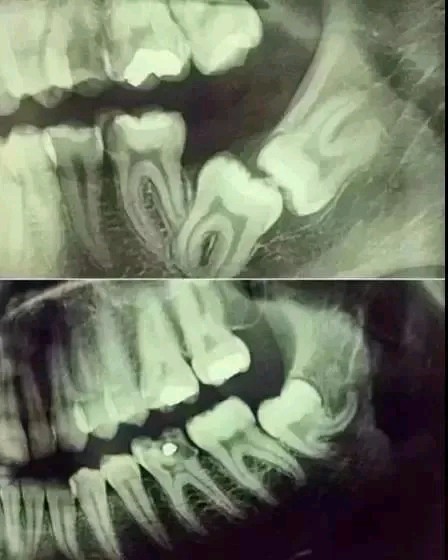

不拍片根本不知道你的牙齿长得会有多奇葩!

X线片一般分为全景片(也就是曲面断层)和根尖片,有些特殊的情况还需要拍CT,具体需要拍哪种片子,一般根据每个人的牙齿情况不同会有区别。

全景片

根尖片